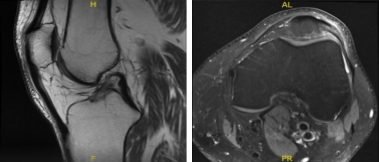

MRI-3T Left Knee Non-contrast

Results for MRI were presented and shown sprain of the medial collateral ligament, without evidence of high-grade tears. Longitudinal vertical tear involving the outer third of the body and posterior horn medial meniscus.